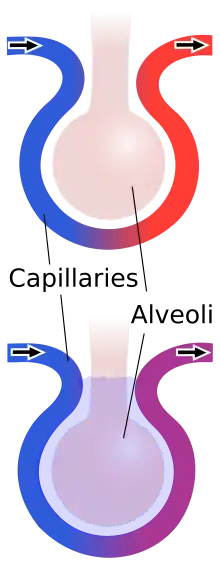

In contusions, torn capillaries leak fluid into the tissues around them.[33] The membrane between alveoli and capillaries is torn; damage to this capillary–alveolar membrane and small blood vessels causes blood and fluids to leak into the alveoli and the interstitial space (the space surrounding cells) of the lung.[11] With more severe trauma, there is a greater amount of edema, bleeding, and tearing of the alveoli.[17] Pulmonary contusion is characterized by microhemorrhages (tiny bleeds) that occur when the alveoli are traumatically separated from airway structures and blood vessels.[24] Blood initially collects in the interstitial space, and then edema occurs by an hour or two after injury.[30] An area of bleeding in the contused lung is commonly surrounded by an area of edema.[24] In normal gas exchange, carbon dioxide diffuses across the endothelium of the capillaries, the interstitial space, and across the alveolar epithelium; oxygen diffuses in the other direction. Fluid accumulation interferes with gas exchange,[34] and can cause the alveoli to fill with proteins and collapse due to edema and bleeding.[24] The larger the area of the injury, the more severe respiratory compromise will be.[17]

Pulmonary contusion can cause parts of the lung to consolidate, alveoli to collapse, and atelectasis (partial or total lung collapse) to occur.[35] Consolidation occurs when the parts of the lung that are normally filled with air fill with material from the pathological condition, such as blood.[36] Over a period of hours after the injury, the alveoli in the injured area thicken and may become consolidated.[24] A decrease in the amount of surfactant produced also contributes to the collapse and consolidation of alveoli;[16] inactivation of surfactant increases their surface tension.[31] Reduced production of surfactant can also occur in surrounding tissue that was not originally injured.[26]

Ventilation/perfusion mismatch

Normally, the ratio of ventilation to perfusion is about one-to-one; the volume of air entering the alveoli (ventilation) is about equal to that of blood in the capillaries around them (perfusion).[40] This ratio is reduced in pulmonary contusion; fluid-filled alveoli cannot fill with air, oxygen does not fully saturate the hemoglobin, and the blood leaves the lung without being fully oxygenated.[41] Insufficient inflation of the lungs, which can result from inadequate mechanical ventilation or an associated injury such as flail chest, can also contribute to the ventilation/perfusion mismatch.[31] As the mismatch between ventilation and perfusion grows, blood oxygen saturation is reduced.[41] Pulmonary hypoxic vasoconstriction, in which blood vessels near the hypoxic alveoli constrict (narrow their diameter) in response to the lowered oxygen levels, can occur in pulmonary contusion.[27] The vascular resistance increases in the contused part of the lung, leading to a decrease in the amount of blood that flows into it,[38] directing blood to better-ventilated areas.[27] Although reducing blood flow to the unventilated alveoli is a way to compensate for the fact that blood passing unventilated alveoli is not oxygenated,[27] the oxygenation of the blood remains lower than normal.[40] If it is severe enough, the hypoxemia resulting from fluid in the alveoli cannot be corrected just by giving supplemental oxygen; this problem is the cause of a large portion of the fatalities that result from trauma.[41]